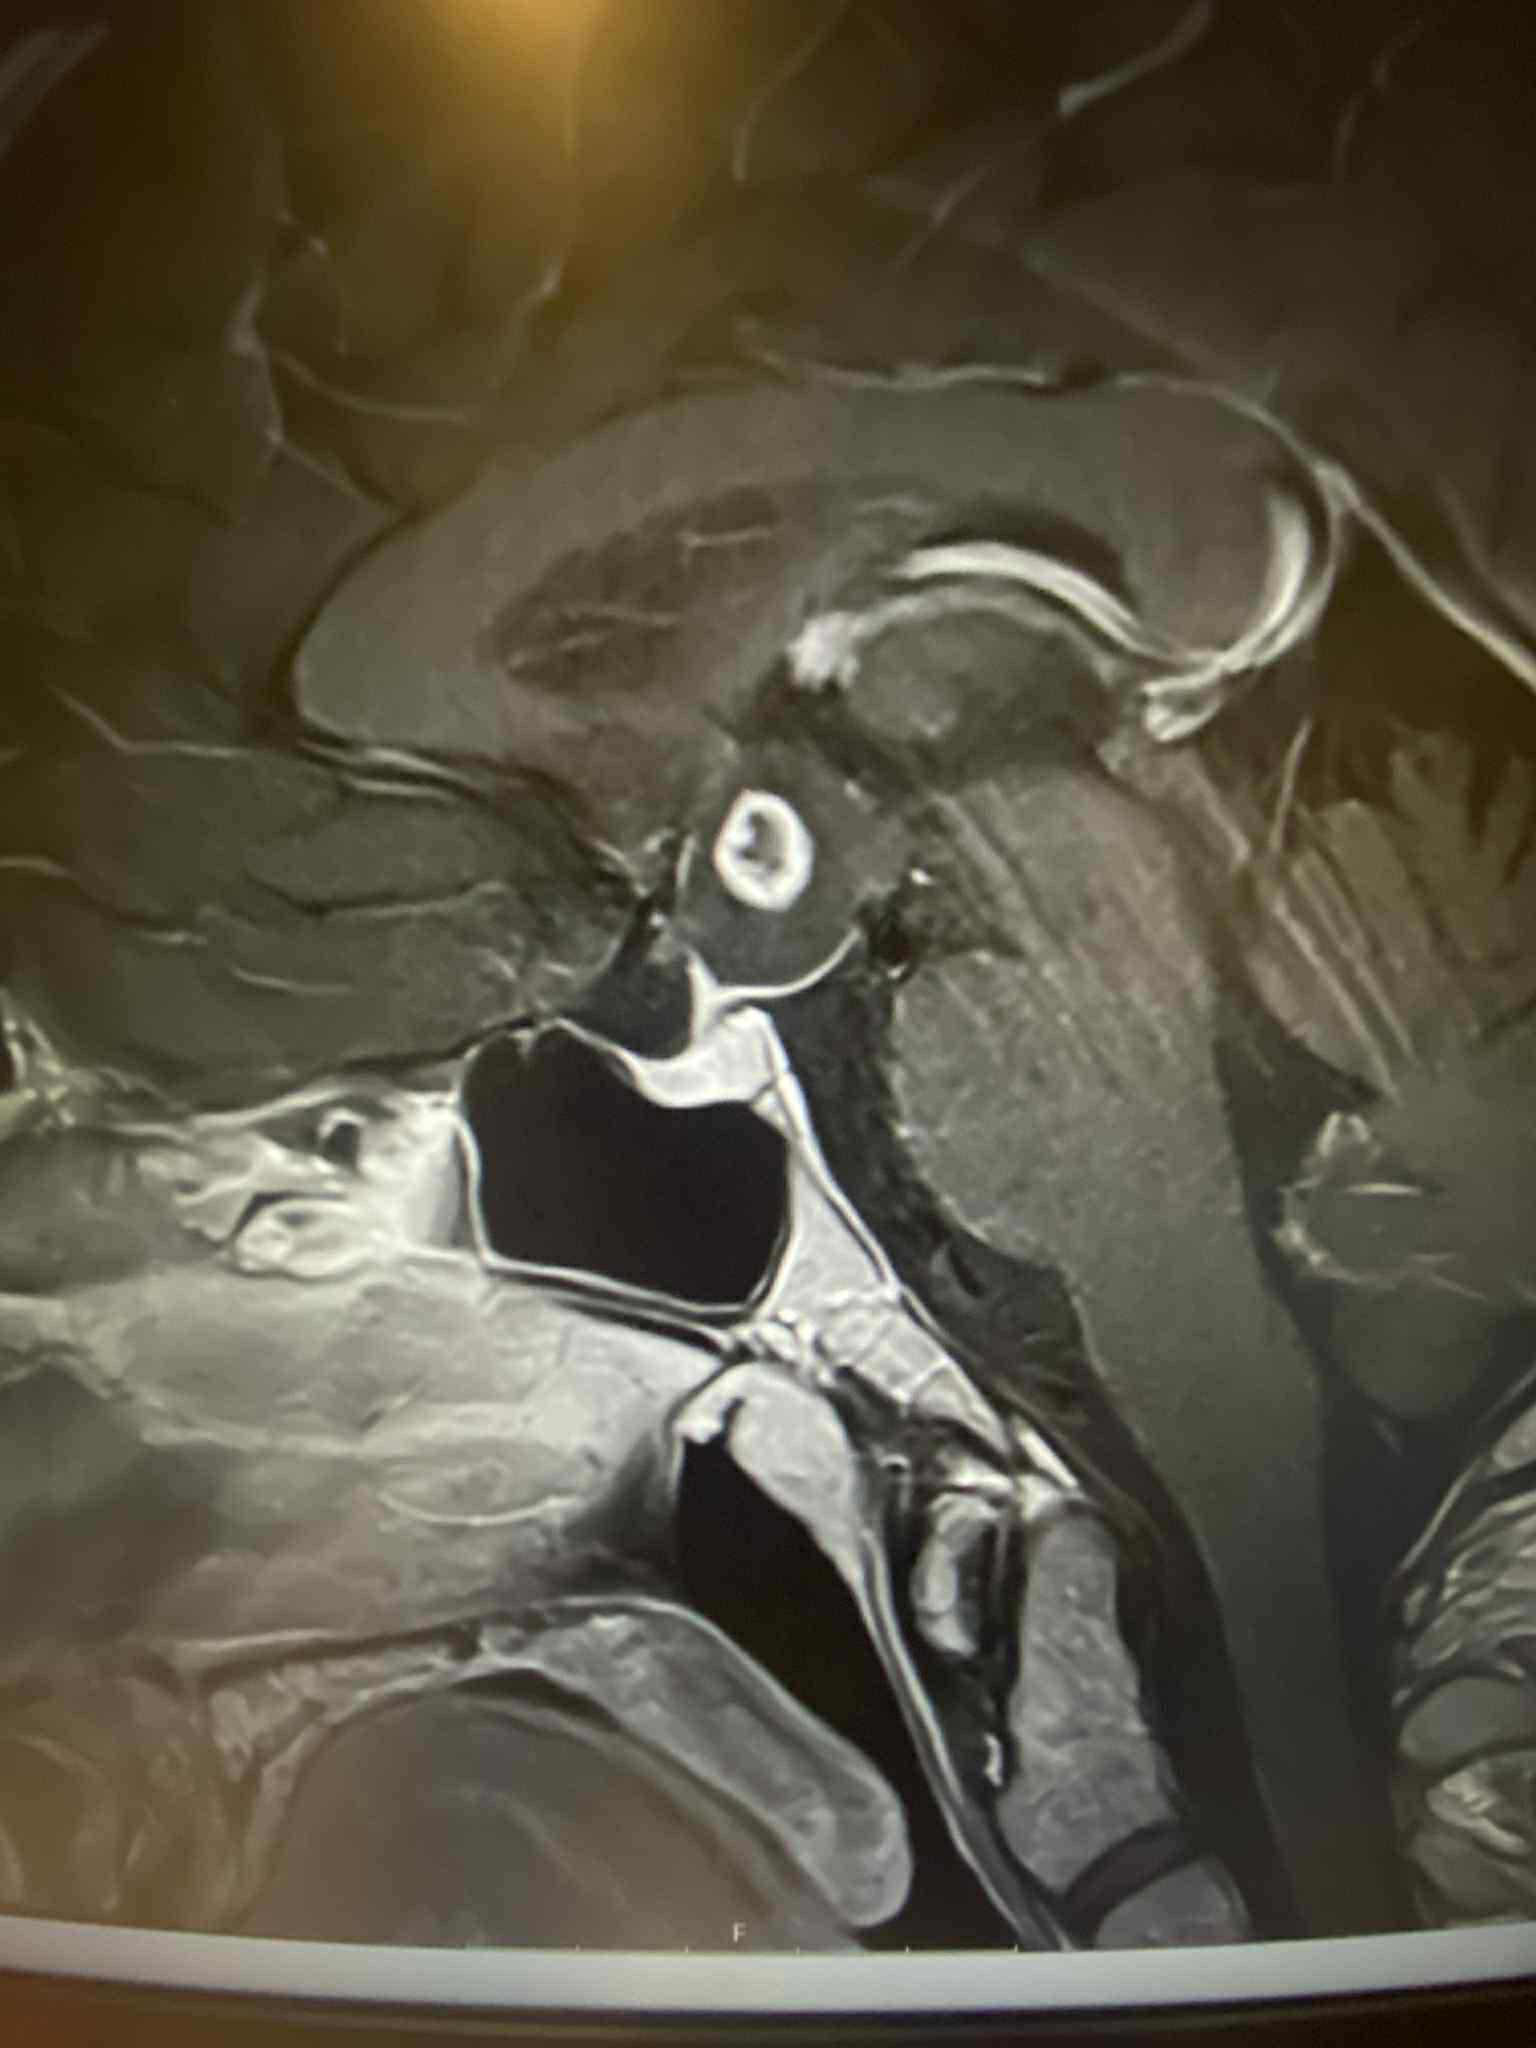

In July he had an MRI done where it showed that he had a tumor on his brain which has grown 4 millimeters as shown by his recent MRI at the start of this month. He has been able to get on an anti-seizure medication but still experiences the nausea, dizziness, headaches and insomnia that the tumor causes. He is at high risk for suffering a stroke due to the tumor pressing up against his hypothalamus.